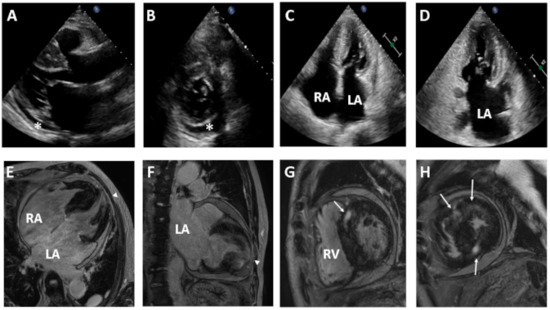

| Diagnosis | Restrictive cardiomyopathy | Hypertrophic cardiomyopathy | Hypertrophic cardiomyopathy |

| Sex/Age(year) | Male/74 | Female/44 | Female/41 |

| Electrocardiography and Holter monitoring | Atrial fibrillation and rare premature ventricular contractions | Sinus rhythm with frequent premature ventricular contractions | Sinus rhythm with rare premature atrial contractions and premature ventricular contractions |

| Transthoracic echocardiography | Biatrial enlargement and pericardial effusion | Asymmetric septal hypertrophy of LV and mildly dilated LA | Asymmetric septal hypertrophy of LV with mild LA enlargement |

| LVEDD 50 mm | LVEDD 40 mm | LVEDD 39 mm | |

| IVS 18 mm | IVS 17 mm | IVS 18.4 mm | |

| EF 60.2% | EF 64.2% | EF 64.2% | |

| E/e’ 14.1 | E/e’ 9 | E/e’ 10.1 | |

| e’ 5.2 cm/s | e’ 9.9 cm/s | e’ 7.5 cm/s | |

| TR peak velocity 3.8 m/s | TR peak velocity 1.8 m/s | TR peak velocity 2.5 m/s | |

| LAVI 115 mL/m2 | LAVI 41 mL/m2 | LAVI 40.1 mL/m2 |